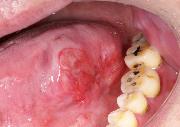

口腔がん

上顎歯肉がん(上あごの歯ぐきのがん)